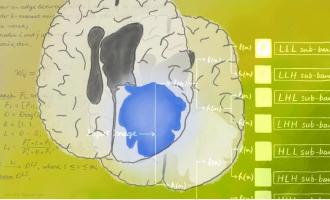

L’INTELLIGENCE ARTIFICIELLE pour prédire la progression des tumeurs

Actualité publiée le 08/02/2023TUMEUR CÉRÉBRALE : Vers un simple test sanguin de détection et d’évaluation